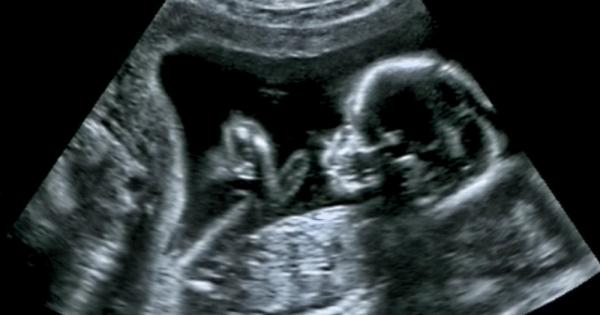

... движения, наподобяващи плач, са свързани с болка или дискомфорт. При изследванията на Рейссланд бебетата ги проявяват без каквато и да било външна стимулация. Източник: Science Alert

...... се бебе, която не може да бъде получена чрез рутинната ултразвукова диагностика при проследяващия акушер-гинеколог. Прочете тайната на ултразвуковите прегледи при фетален специалист на jenata.blitz.bg

...... рутинната ултразвукова диагностика при проследяващия акушер-гинеколог.Вижте какви изследвания трябва да направи всяка бременна жена при сертифициран специалист по фетална медицина през 9-те месеца на jenata.blitz.bg